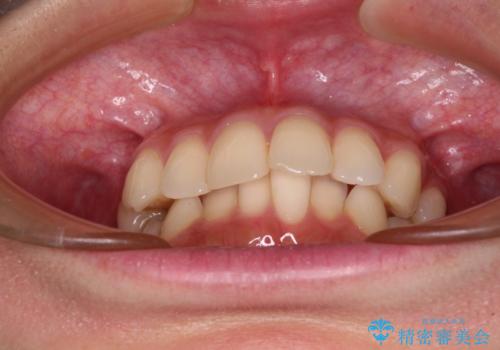

- 前歯のデコボコと強い咬みしめを気にして来院された患者様です。

インビザラインを用いて、前歯の叢生を解消するとともに、ディープバイトを改善していくこととしました。

海外へ転居する予定があったため、1日22時間以上の装着時間をしっかりと守っていただき、予定期間よりも早く、思っていた以上にきれいに仕上げることができました。